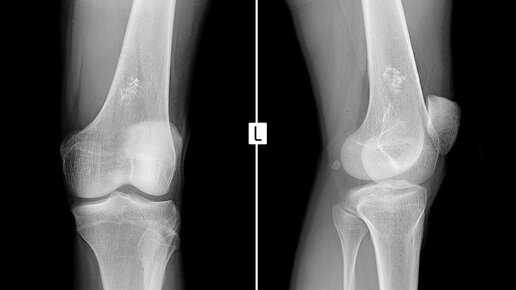

Саркома Юинга — редкая форма рака, которая поражает кости или мягкие ткани, окружающие кости. 4 стадия саркомы Юинга — самая запущенная стадия заболевания. На этой стадии рак распространяется на отдаленные ткани и органы. На ранних стадиях человек может иметь такие симптомы, как боль в костях, отек и скованность. Если заболевание прогрессирует до 4-й стадии, пациент будет иметь дополнительные симптомы, такие как лихорадка и снижение веса. На всех стадиях заболевания лечение обычно состоит из химиотерапии, хирургического вмешательства, а иногда и лучевой терапии...

Саркома Юинга — редкий тип рака, поражающий кости или мягкие ткани, окружающие кости. Этот тип рака имеет тенденцию к быстрому распространению, что может повлиять на показатели выживаемости. Саркома Юинга чаще всего поражает детей и молодых людей, хотя может развиться и у пожилых людей. Возраст человека на момент постановки диагноза может сыграть определенную роль в его прогнозе. Саркома Юинга — выживаемость у взрослых Имеются противоречивые данные относительно того, хуже ли выживаемость при саркоме Юинга у взрослых, чем у детей...